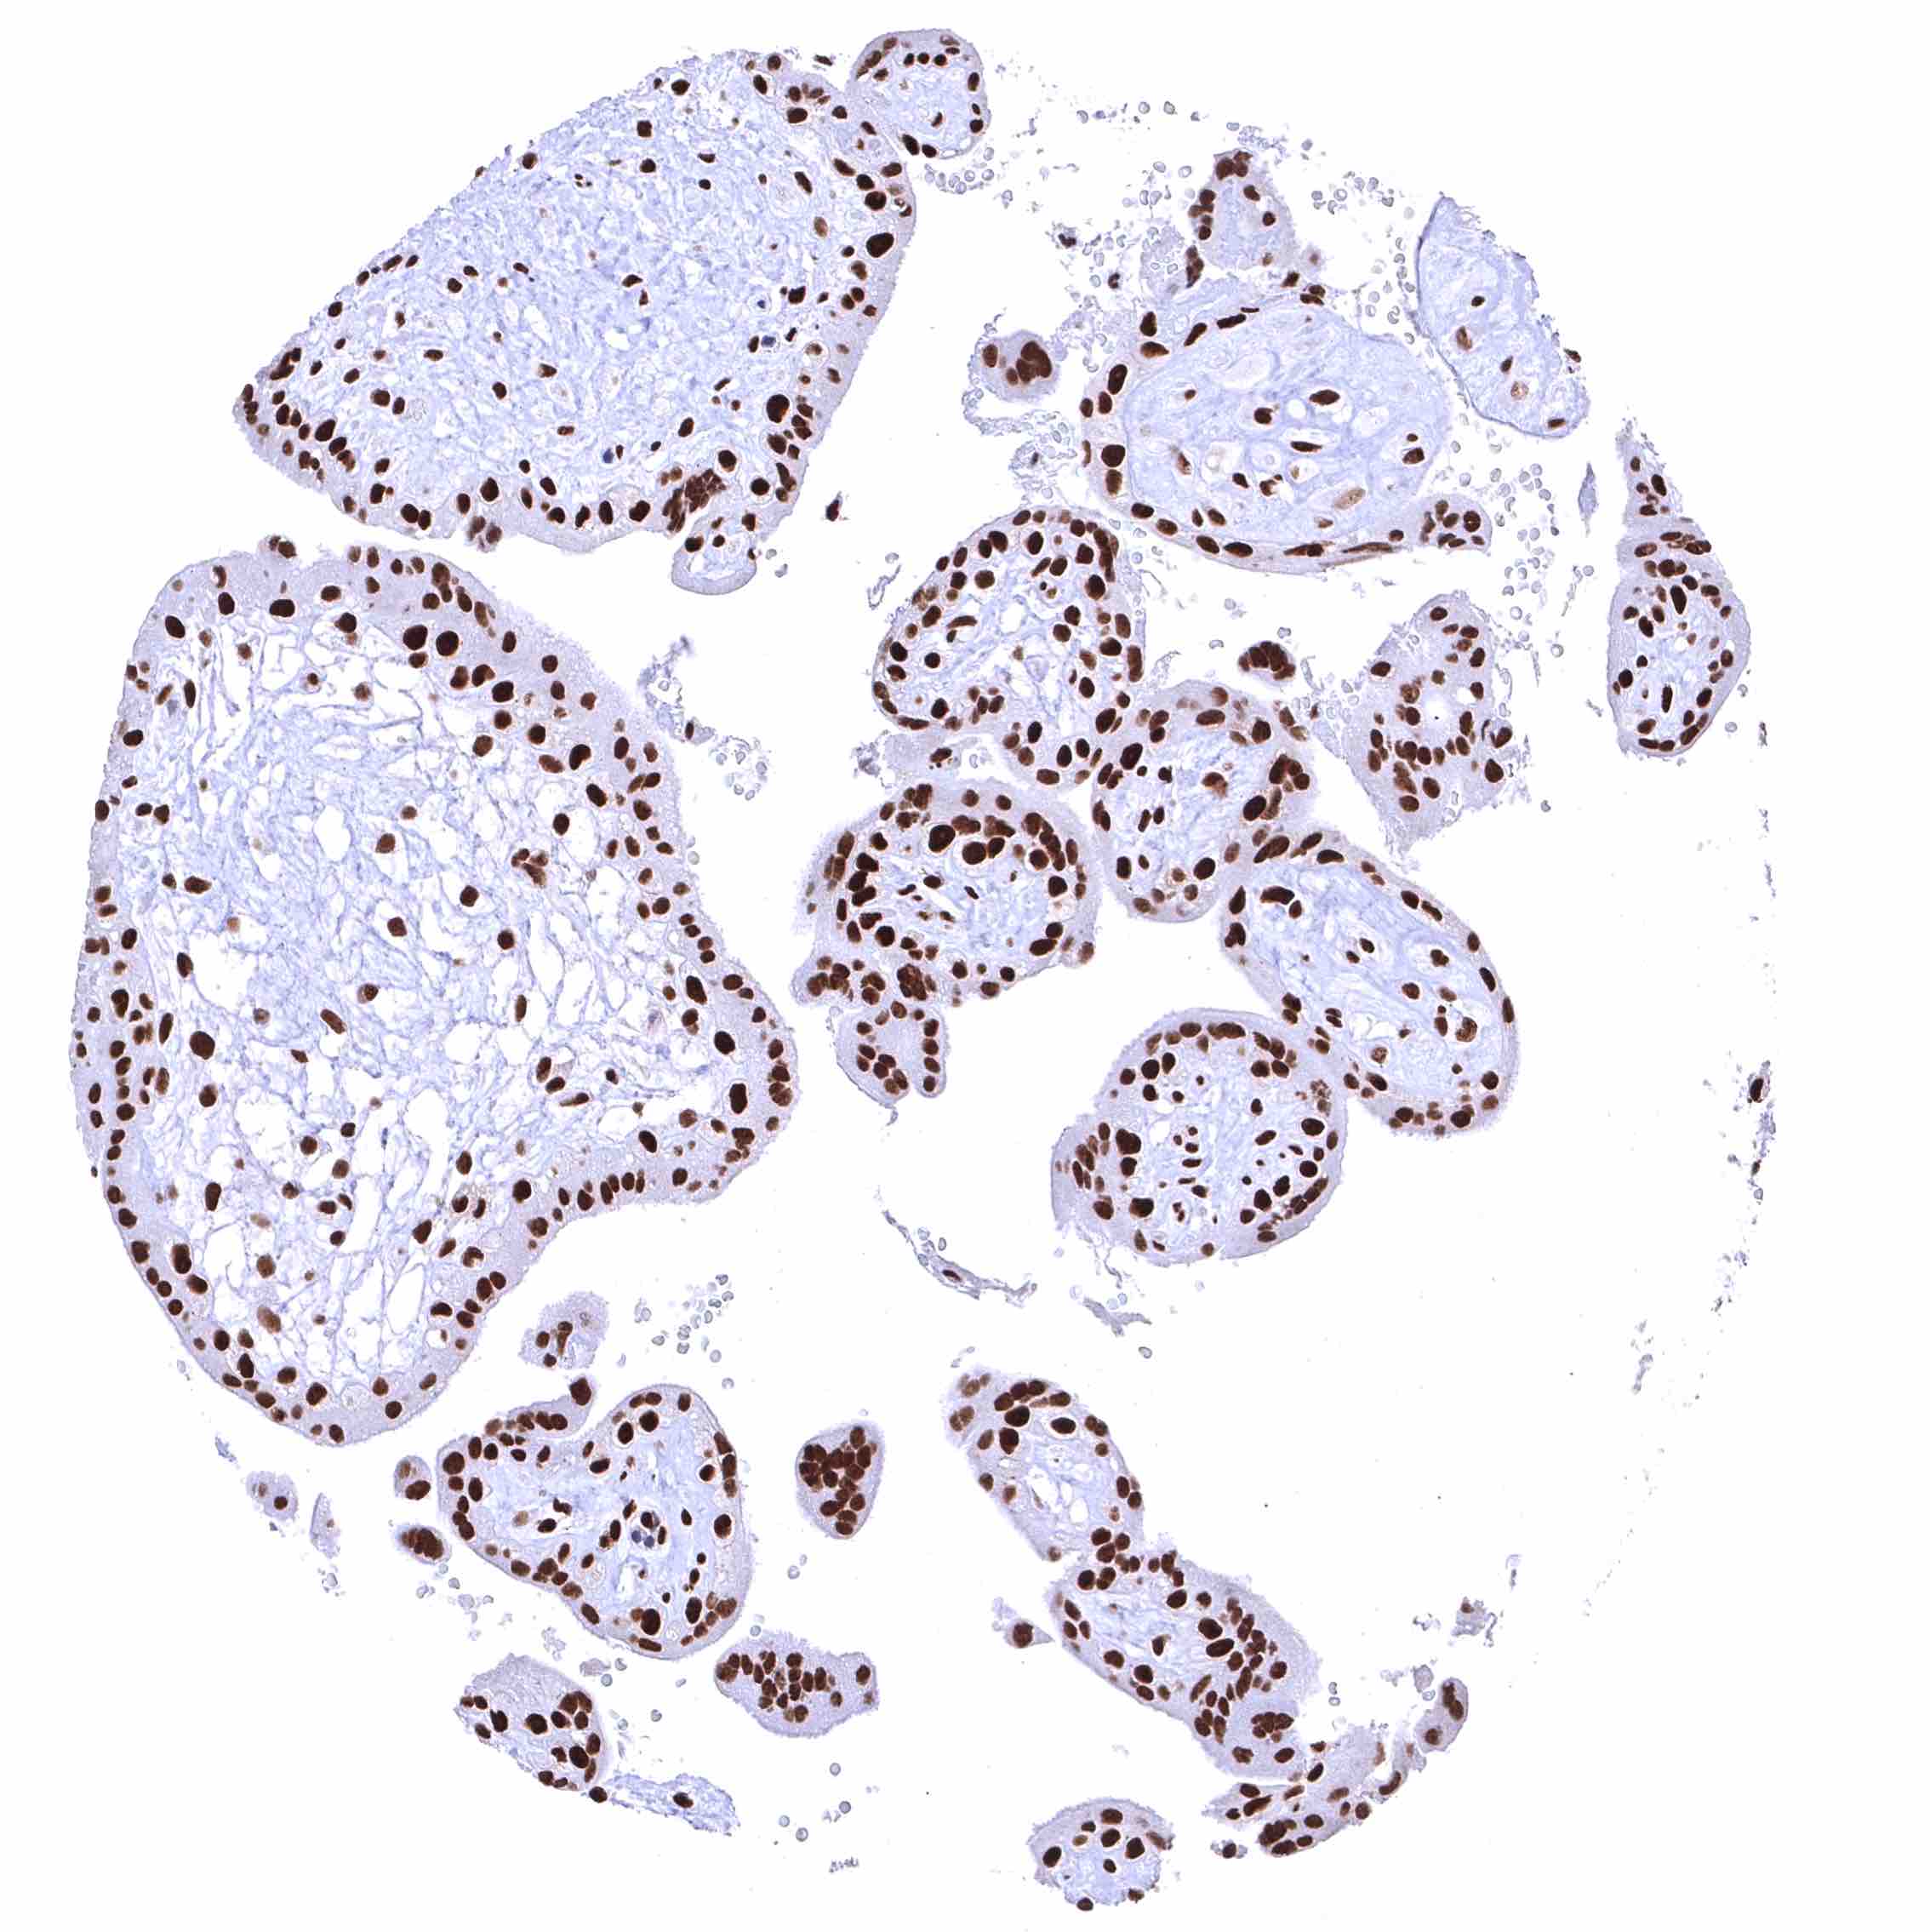

BRD4 antibody [HMV4275] HistoMAX™

Placenta, early – Nuclear BRD4 staining is particularly strong in all trophoblast cells.